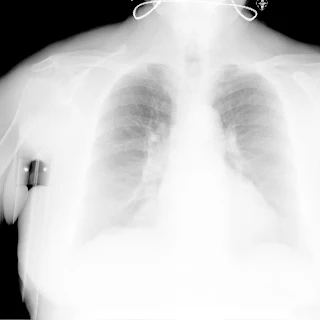

Флюорограма №86

Легені без вогнищево - інфільтративних змін. Корені ущільнені. Синуси вільні. Серце розширене. Праворуч тінь від милиці.